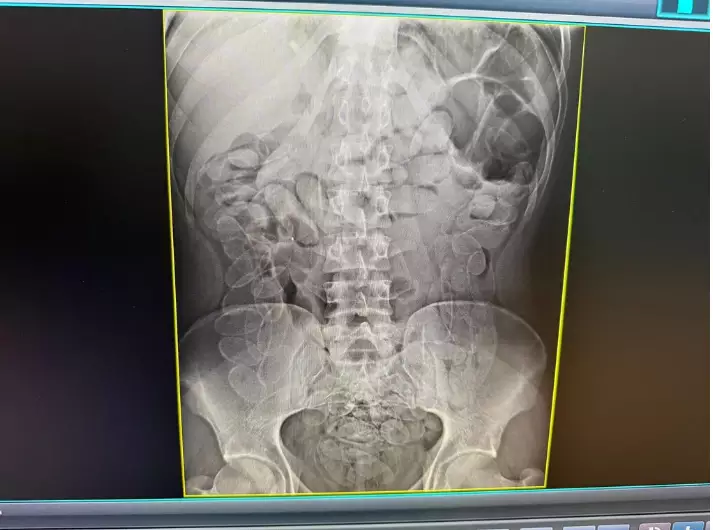

Um exame de raio-X realizado na região abdominal identificou diversos invólucros no estômago, confirmando a presença do entorpecente.